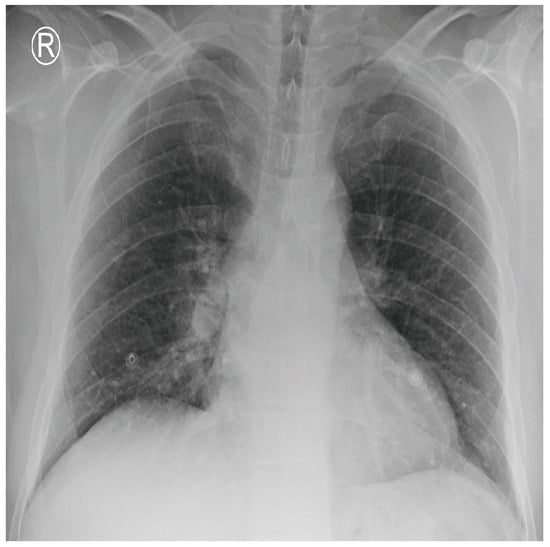

COVID-19 patients who have clinical symptoms are more likely to show abnormal CXR [9]. The main findings of recent studies suggest that these lung images display patchy or diffuse reticular–nodular opacities and consolidation, with basal, peripheral, and bilateral predominance [10]. For example, Figure 1 shows the CXR of a mild case of lung tissue involvement with right infrahilar reticular–nodular opacity. Moreover, Figure 2 shows the CXR of a moderate to severe case of lung tissue involvement. This CXR shows right lower zone lung consolidation and diffuse bilateral airspace reticular–nodular opacities, which are more prominent on peripheral parts of lower zones. Similarly, Figure 3 shows the CXR of a severe case of lung tissue involvement. This is caused by diffuse bilateral airspace reticular–nodular opacities that are more prominent on peripheral parts of the lower zones, and ground glass opacity in both lungs predominant in mid-zones and lower zones. On the other hand, Figure 4 shows an unremarkable CXR with clear lungs and acute costophrenic angles (i.e., normal).

Figure 3.

CXR of COVID-19 subject showing severe lung tissue involvement.